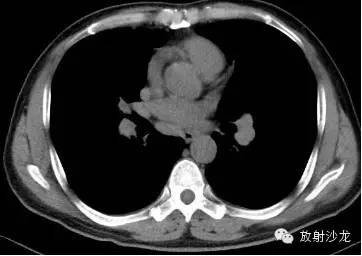

第一例:

44岁女性,因左乳腺结节行胸部CT检查发现胸部病变。

三幅图为典型的胸部结节病表现,肺门纵隔多发淋巴结肿大,各淋巴结不融合、不坏死、不侵犯邻近结构。右侧气管旁、右侧肺门、左侧肺门、主肺动脉窗淋巴结肿大,为1,2,3,4淋巴结。

双肺底见间质性病变。

CT拟诊结节病,呼吸内科建议定期观察。未经任何治疗11个月后复查示肺门纵隔淋巴结正常,双肺底间质性病变消失。左乳腺结节无变化(图略)